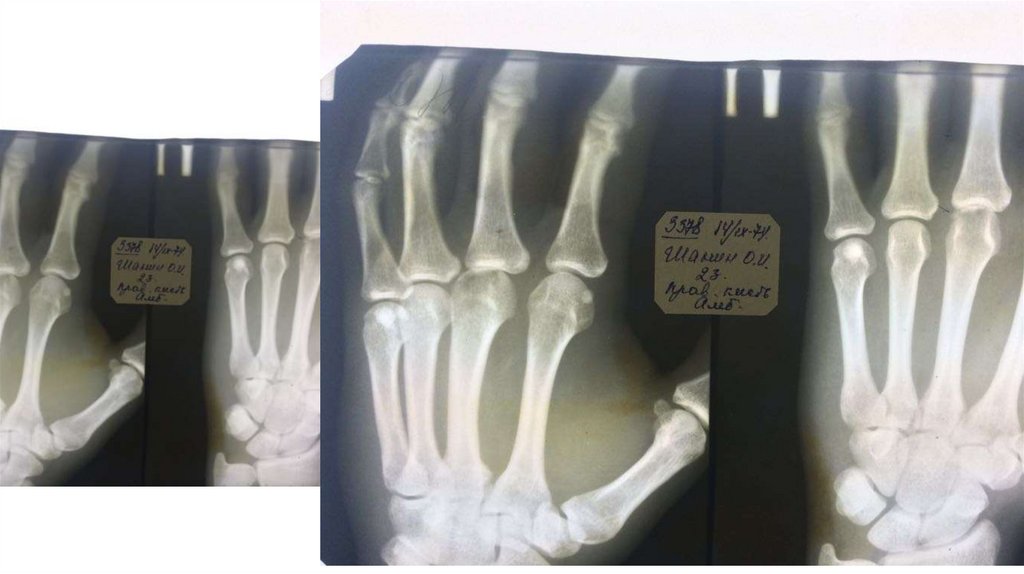

Воспалительные заболевания опорнодвигательного аппарата

«Воспалительные

заболевания опорнодвигательного аппарата»